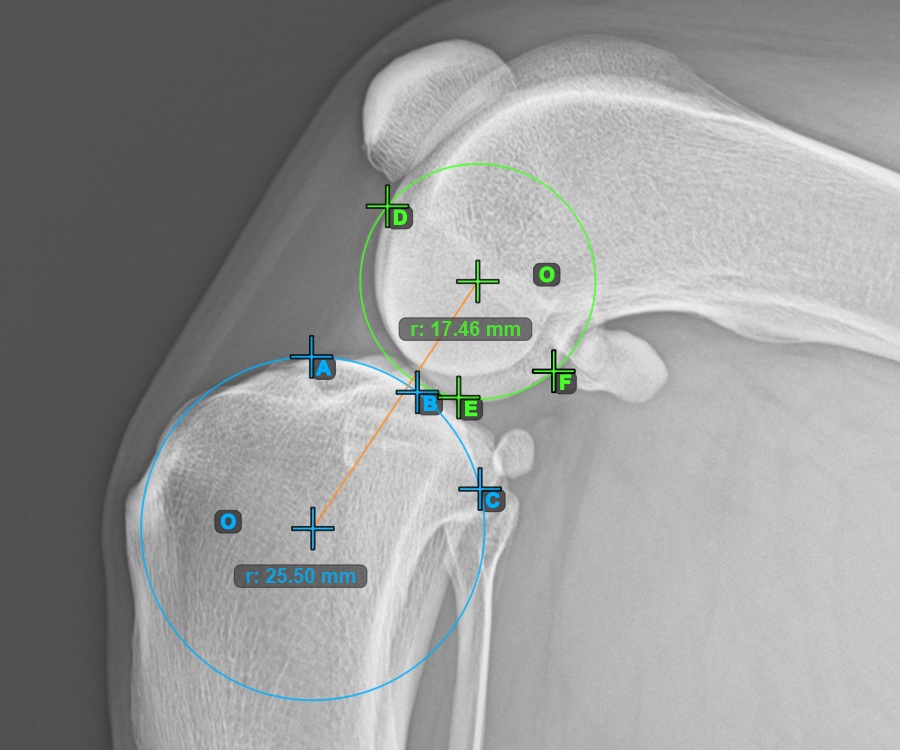

Mark the three points on the inner (secondary) condylus of the femoral bone (Condylus Femoris). Regardless of the order, make sure to mark the most cranial point, the most caudal point and the midpoint of the Condylus Femoris. A circle will be automatically constructed based on the three placed points.

The image below represents a typical placement of the three points on the second Condylus Femoris.